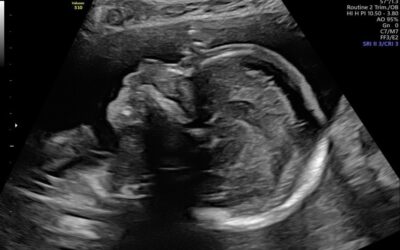

Echocentrum Almere biedt zwangere vrouwen en vrouwen met een kinderwens uit heel Almere hoogwaardige echoscopie in een warme en persoonlijke sfeer. In samenwerking met Verloskundig Centrum Kroonprins combineren wij medische deskundigheid met aandacht en rust.

Je kunt bij ons terecht van kinderwens tot zwangerschap: voor fertiliteitsecho’s, medische echo’s, pretecho’s én anticonceptiezorg waaronder spiraal en implanon plaatsing. Met moderne 3D/4D-techniek, ervaren echoscopistes en met meer dan 2000 echo’s per jaar garanderen wij aandacht, kwaliteit, veiligheid en een bijzondere echobeleving.

De twintig weken echo is een uitgebreide medische echo tussen 18 en 22 weken waarbij gekeken wordt of de baby mogelijk aangeboren afwijkingen heeft.

De kwaliteit van de echo’s is fantastisch. De 3D en 4D beelden gaven ons een prachtig inzicht in de ontwikkeling van onze baby.